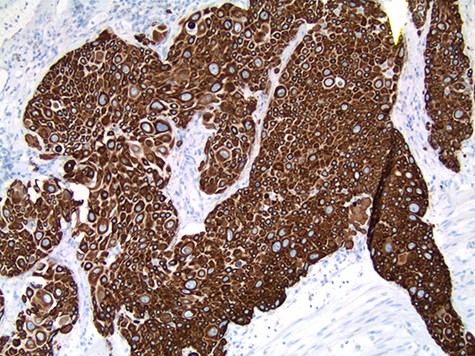

The patient’s post-operative course was complicated by dysphagia requiring gastrostomy tube placement. Surveillance imaging of the chest showed extensive mediastinal, hilar and supraclavicular lymphadenopathy with new pulmonary nodules and a large mediastinal mass encasing the trachea and ascending aorta consistent with distant metastatic disease. Cardiothoracic surgery was consulted and deemed the mass unresectable. On subsequent follow up, the patient endorsed a 2-year history of melena and was referred to gastroenterology for colonoscopy. However, prior to the scheduled colonoscopy, the patient was found to have abdominal distention with imaging confirming colonic pneumatosis and a large mass in the ascending colon. The patient’s clinical condition deteriorated despite non-operative management. He underwent exploratory laparotomy with right hemicolectomy, transverse colectomy and end ileostomy. Pathology workup included concurrent comparison of the salivary gland and colonic tumors, which showed similar histologic features. p63 and CK5/6 immunohistochemistry stain positivity in the colonic tumor confirmed the presence of SCC. CK20 and CDX2 immunostains to exclude a colonic primary adenocarcinoma or adenosquamous carcinoma were negative. In addition, due to the unusual initial presentation of a squamous appearing tumor in the submandibular gland, a MAML2 (11q21) rearrangement FISH study to rule out mucoepidermoid carcinoma (with squamous predominating features) was performed and was negative (Figs 3 and 4).